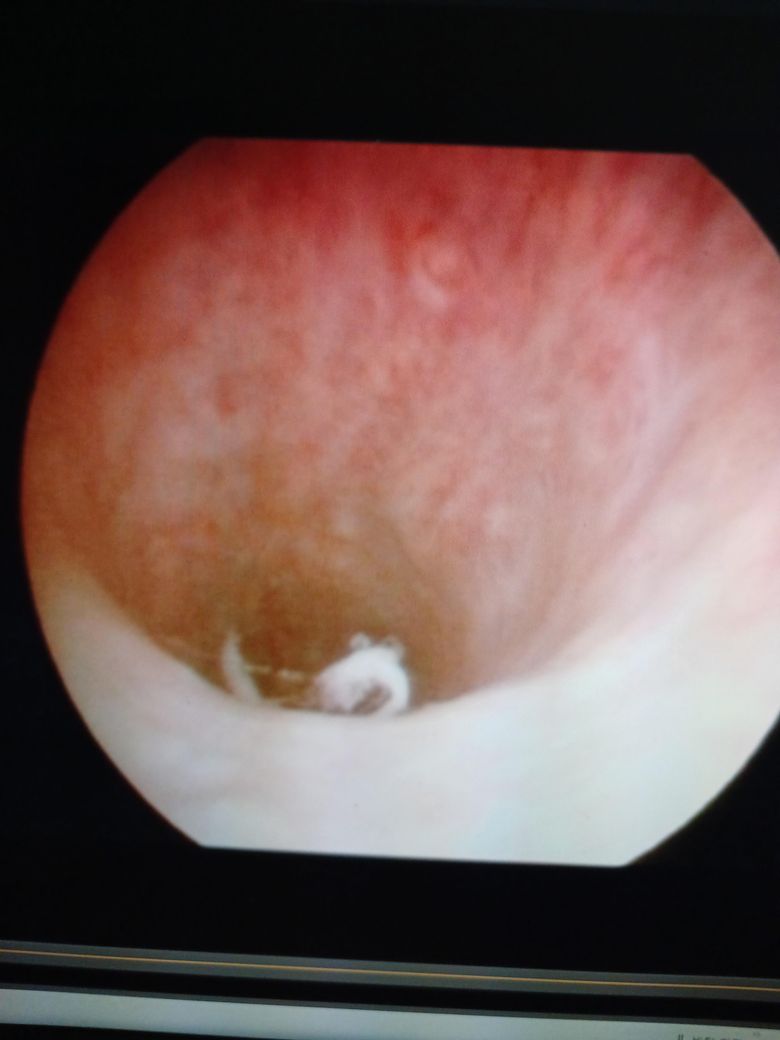

먼저 사진을 몇 장 보내드립니다방광 내시경을 했습니다 그런데 점막 부위에 껍질이 좀 벗겨진 것을 볼 수가 있었습니다 이 점막껍질은 떨어져 나가나요 만약에.껍질이 벗겨지고 소변

방광 내시경을 했습니다 그런데 점막 부위에 껍질이 좀 벗겨진 것을 볼 수가 있었습니다 이 점막껍질은 떨어져 나가나요 만약에.껍질이 벗겨지고 소변과함께 떨어져 나가나요

껍질에 벗겨진 부분에 이물질 것이 묻어 있다면 점막 재생 되면서 탈락과

재생이반복되면서 함께 나중에 떨어져 나가나요

• 1번 째 사진

점막이 탈락되면서 소변으로 저절로 빠져 나갑니다.

내시경 사진으로 보아 더 크게 느껴지는 것이지, 실제 크기는 무척이나 작아 육안으로 자세히 봐야 보일 정도입니다.

크게 걱정하지 않으셔도 될 것으로 판단됩니다.